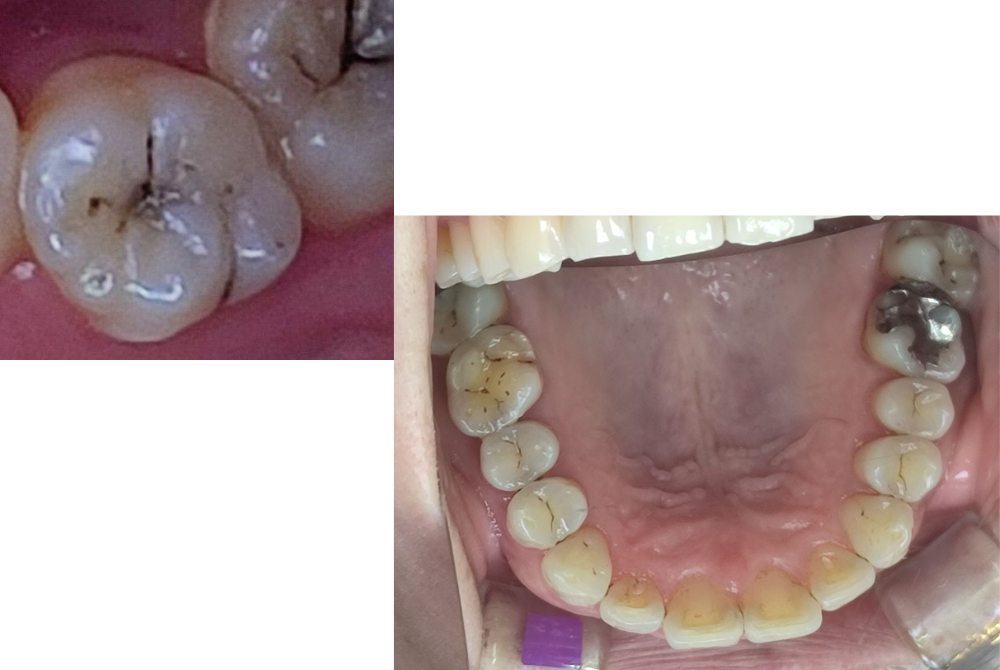

C2(象牙質に達した虫歯)

冷たいものがしみる、甘いもので違和感を覚える──そんな症状が出るのがC2です。

虫歯の進行がやや進んでおり、後述のCRや詰め物(インレーなど)で対応します。